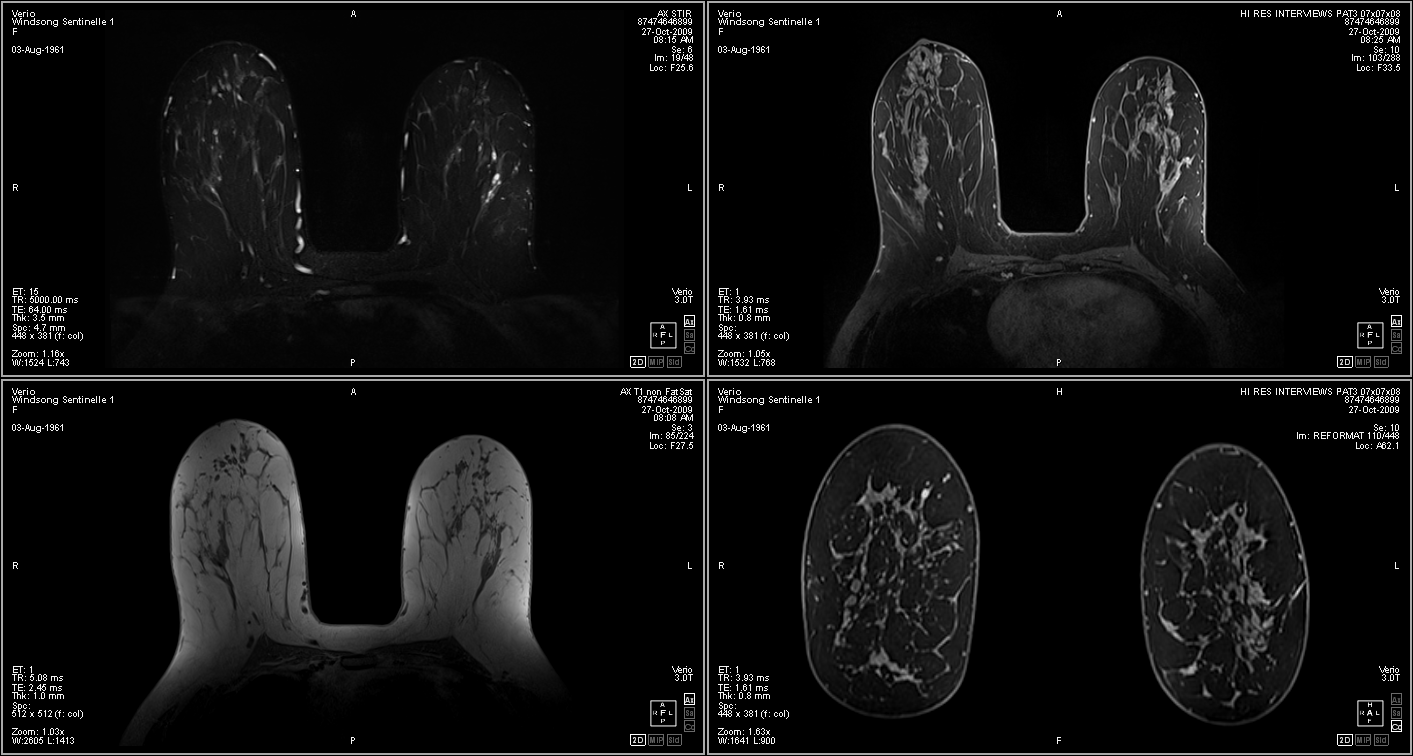

Product Brochure and MRI Sample Image

8-Channel Bilateral Imaging Setup

Complete System

MRI Image Produced by this System